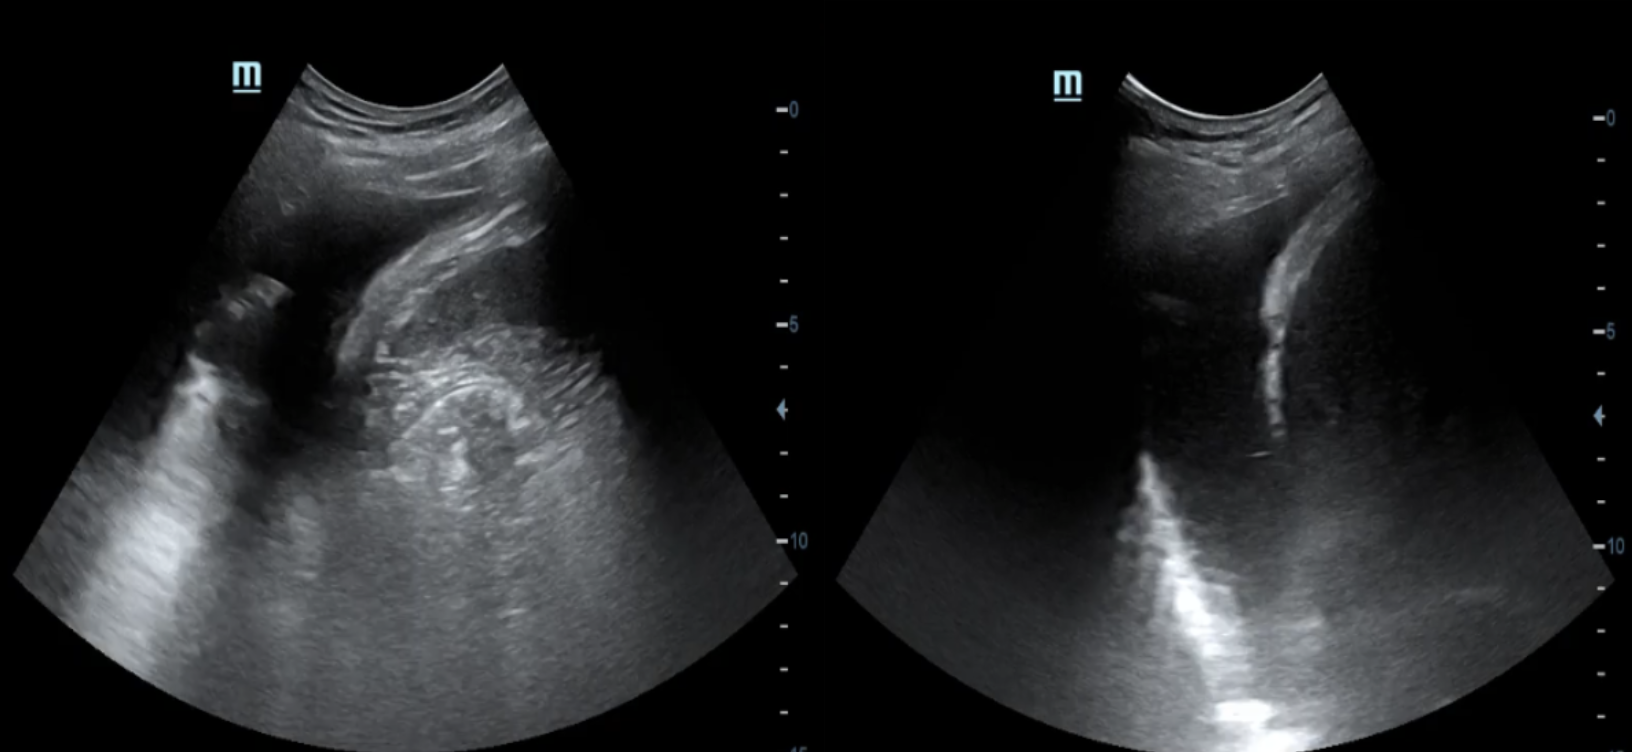

Descripción de los hallazgos ecográficos y las imágenes más relevantes para la resolución del caso

A la exploración ecográfica pulmonar se objetivan líneas B en ambos campos anteriores y superiores, así como derrame pleural bilateral, orientando la causa de la disnea hacia la insuficiencia cardíaca.

A nivel cardiológico, observamos una disminución de la fracción de eyección y un aumento de la presión venosa central.